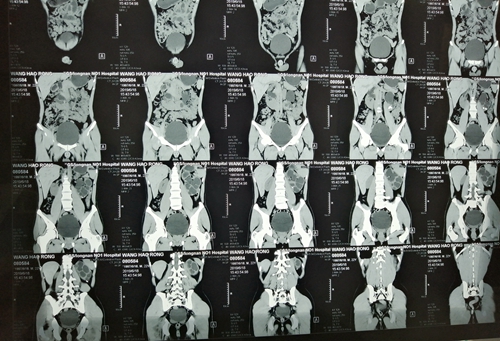

近日,我院泌尿外科成功为一名马蹄肾畸形合并肾结石的患者实施了经皮肾镜碎石术。

22岁的患者王某,因右侧腰背部间断性疼痛不适1月余来我院泌尿外科就诊。入院后,行CT检查提示:右肾结石并积水,检查发现存在马蹄肾合并肾结石,手术难度大。泌尿外科主任李朝明立即带领科室医生认真讨论病情,根据患者情况权衡利弊,最终定下经皮肾镜碎石术的手术方案。

6月28日,在李朝明的指导下,我院泌尿外科成功为患者实施了经皮肾镜碎石术,手术顺利,碎石效果显著,术后患者恢复良好,复查未见结石残余,现已康复出院。